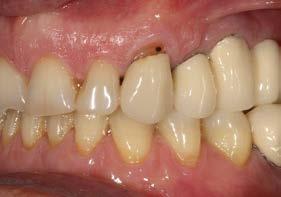

Explantación atraumática y recambio de implantes mal posicionados y afectados por periimplantitis sumado a la utilización de implantes estrechos y cortos. Enfoque mínimamente invasivo de un caso de atrofia ósea moderada

42 | INVESTIGACIÓN CLÍNICA